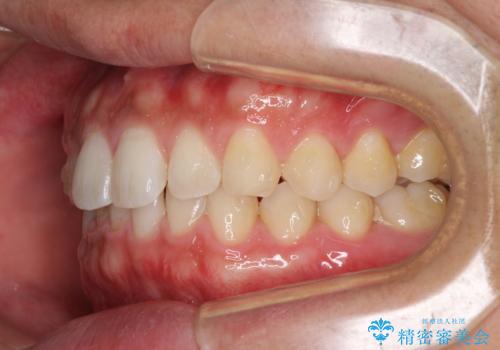

細かい隙間にものがはさまる インビザラインによる矯正治療

- 上下の前歯の隙間を気にして来院された患者様です。

インビザラインを用い、上下歯列のスペースを閉じていくこととしました。

銀行にお勤めのため、突然の転勤により通院が大変な状況となりましたが、インビザラインであれば2-3ヶ月に1度を目安に来院いただき、無事に治療を終えることができました。